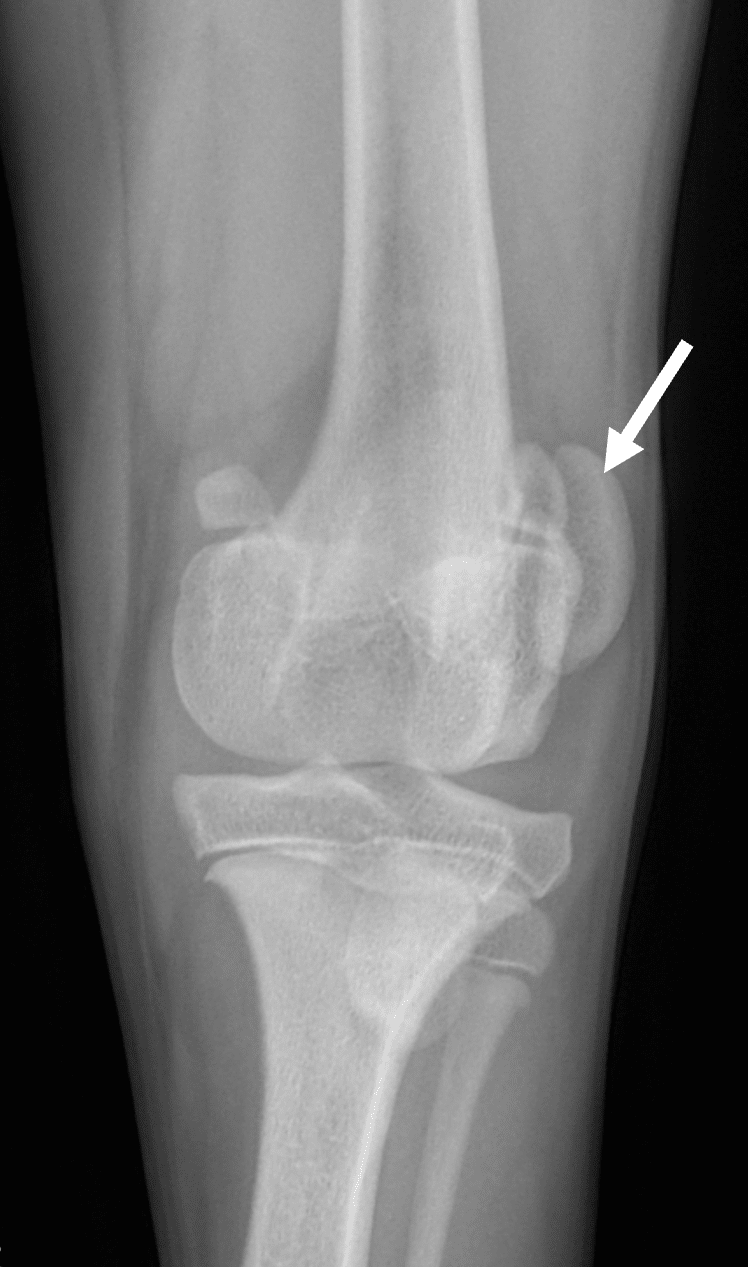

La rotule chez le chien (également appelée patelle), est un os situé dans le tendon du muscle quadriceps. Ce petit os coulisse au contact du fémur en fonction des différents degrés de flexion/extension du genou dans une fosse osseuse (la trochlée) située dans l’articulation du genou. La rotule est rattachée plus bas au niveau du tibia par un tendon (le tendon patellaire). Le muscle quadriceps, la rotule, le tendon patellaire et la tubérosité tibiale forment l’appareil extenseur du genou, ils permettent de réaliser des flexions et extensions du genou et sont normalement parfaitement alignés l’un par rapport à l’autre.

La rotule (également appelée patelle) est un os situé dans le tendon du muscle quadriceps. Ce petit os coulisse au contact du fémur en fonction des différents degrés de flexion/extension du genou dans une fosse osseuse (la trochlée) située dans l’articulation du genou. La rotule est rattachée plus bas au niveau du tibia par un ligament (formant le tendon patellaire). Le muscle quadriceps, la rotule, le tendon patellaire et la tubérosité tibiale forment l’appareil extenseur du genou, ils permettent de réaliser des flexions et extension du genou et sont normalement parfaitement alignés l’un par rapport à l’autre.

On parle de luxation de la rotule à partir du moment où la rotule sort de son logement lors des mouvements de flexion/extension. Cette luxation peut être médiale (vers l’intérieur du genou) ou latérale (vers l’extérieur), permanente ou occasionnelle, réductible (la rotule peut revenir spontanément en place dans son logement) ou non, coercible (lorsque la rotule est remise en place, celle-ci tient) ou non. C’est de cette façon que l’on grade une luxation de rotule :

Parfois, c’est une conformation anormale de la hanche, une malformation du fémur ou du tibia, ou une déviation de la crête tibiale qui peuvent être à l’origine d’une luxation de la rotule. Enfin, la trochlée dans laquelle glisse la rotule manque souvent de profondeur pour accueillir et maintenir la rotule en position.